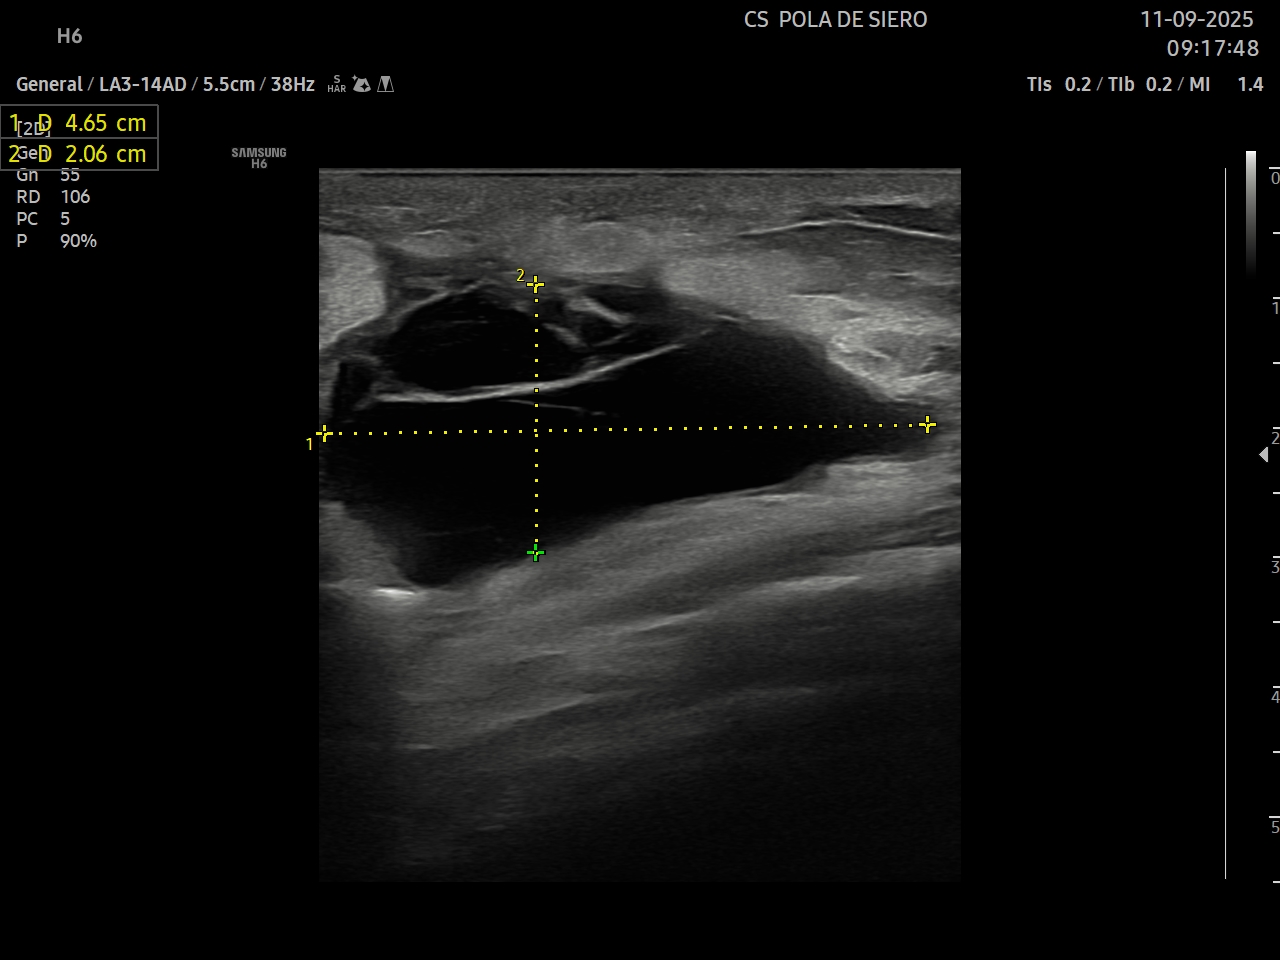

Ante la sospecha de infección local se realiza ecografía clínica para realizar diagnóstico diferencial entre celulitis y absceso de cara a un adecuado manejo del paciente.

Hallazgos ecográficos

Se identifica en el tejido celular subcutáneo una colección líquida, mal definida, de contornos irregulares, predominantemente hipoecoica con áreas ecogénicas en su interior. La lesión muestra refuerzo acústico posterior como corresponde a los contenidos líquidos. Con Doppler color presenta aumento de flujo periférico con escasa vascularización en su interior.

El diagnóstico diferencial se realizó entre celulitis y absceso. En este caso, fue diagnosticado de absceso en zona de la herida quirúrgica.